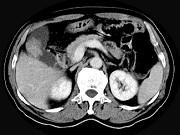

问题 男,45岁,右季肋区疼痛,Murphy征阳性,B超提示胆囊息肉,CT所见如图,最可能的诊断是()

选项 A.胆囊息肉 B.胆囊癌 C.慢性胆囊炎 D.胆囊转移癌 E.胆囊腺肌增生症

答案 B